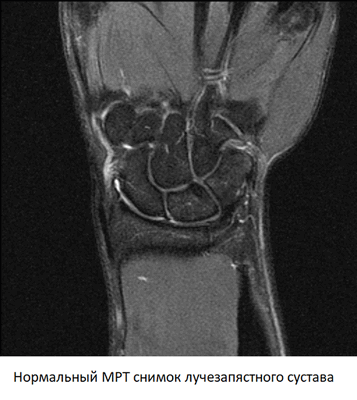

МРТ лучезапястного сустава, что показывает

МРТ лучезапястного сустава — метод диагностики болезней и травм сложного сочленения, образованного костями запястья и суставной поверхностью лучевой кости. Безопасность и точность процедуры обусловлена использованием явления магнитного резонанса, для получения которого оборудование генерирует магнитное поле. Метод не связан с рентгеновским или иным ионизирующим излучением и не несет лучевой нагрузки, отрицательно влияющей на организм пациента.

Что покажет МРТ лучезапястного сустава

Снимки, полученные с помощью МРТ — это серия срезов толщиной от 1 мм, сделанная через область обследования в нескольких плоскостях. На них четко видны кости, образующие лучезапястный сустав, суставная полость и суставной хрящ, оболочка сочленения, связки, мышцы и их сухожилия.

При расшифровке снимков врач обращает внимание на ширину суставной щели, состояние хряща и суставной оболочки, целостность связочного аппарата. При наличии объемных образований МРТ позволяет с высокой точностью определить, что это — киста или опухоль. Изучая динамику накопления контраста, можно выявить ранние признаки воспаления или злокачественного процесса.